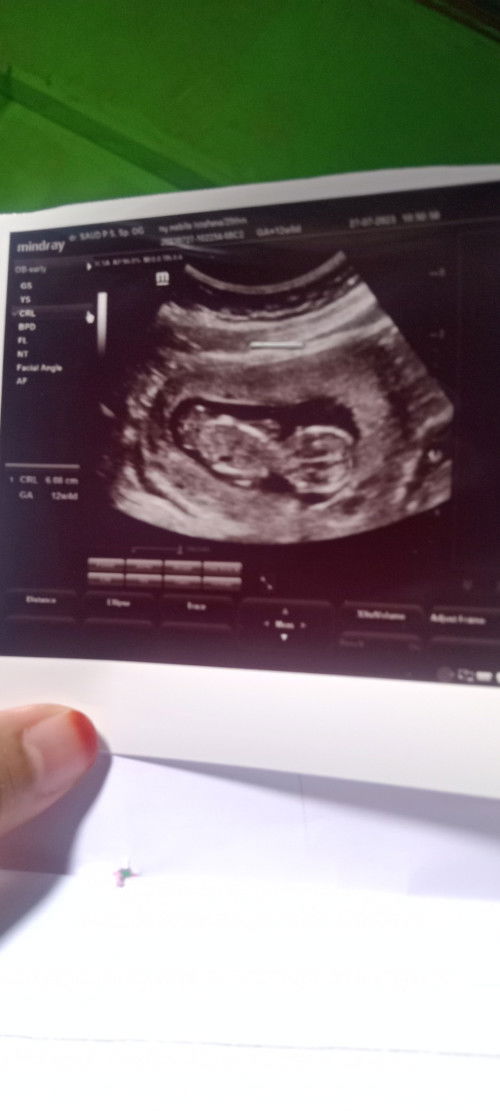

Kan tadi saya USG apakah 12 Minggu 6 hari panjang 6,8 normal ya bund. ,saya sering minum es soalnya

6.8 itu 12w6d itu normal banget bun, tinggi nanti bayi nya. minum es ga ngaruh ke panjang harusnya bun, tapi ke berat..

tp di situ gaada tampilan BB nya .dokternya jg gada blg BB nya

ini brpa Dimensi y Bun

gatau Bun soalnya gaada keterangan sejelas mungkin Kya kurang detail .kayanya 2 d bund